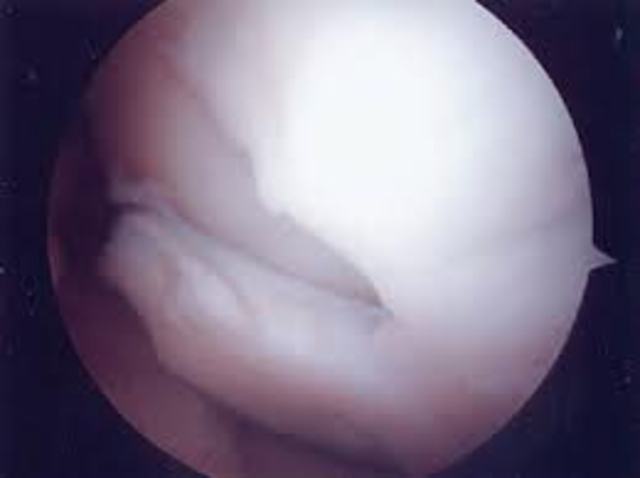

Chondux

Fué desarrollado en 2008 por la compañía californiana Cartilix.Consiste en un hidrogel de polímeros que, una vez inyectado en la rodilla durante la operación, guía la regeneración del cartílago estimulando a las células del cuerpo.